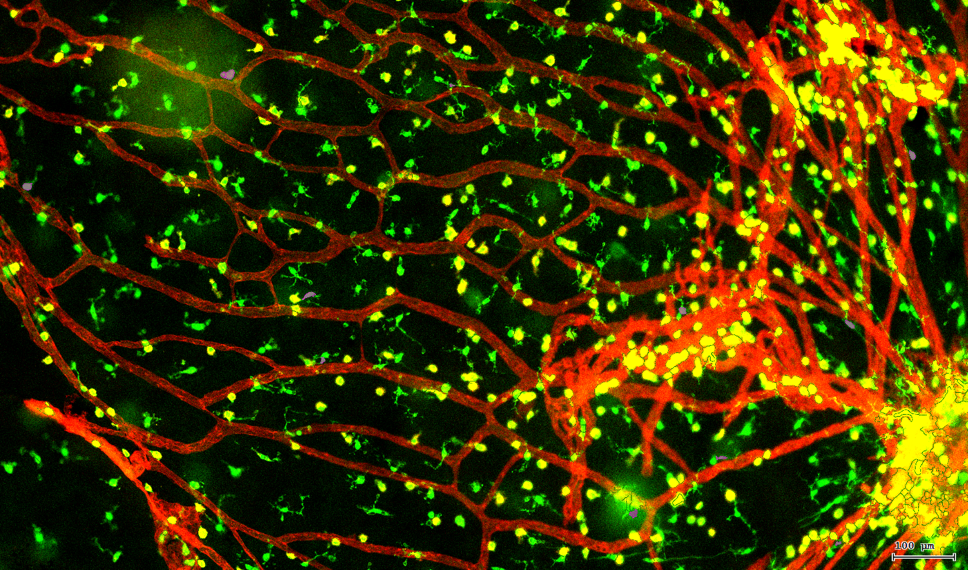

视网膜荧光样本中小胶质细胞胞体、神经纤维识别、血管识别、血管斑点识别、神经元与血管的距离分析。

3. 根据FITC通道识别神经胞体并筛选出有效细胞胞体(细胞核识别算法)。

4. 膜识别FITC染色信号的区域确定神经纤维,并对不同长度神经纤维进行分类。

5. 识别血管的Texa Red染色区域面积及强度。

6. 计算神经元与血管间的空间距离,并统计数量和占比。

7. 根据毛细血管亮斑的识别结果,统计新生小血管数量。

根据染色强度,染色面积,细胞形态学,利用正反向回溯功能和设门圈选Gating,排除杂质,细胞碎片,黏连细胞(绿色框线标记),获得有效的神经元胞体,(粉色框线标记),并将胞体按照面积分为两类(散点图)。

由于该视网膜样本是标记的小胶质细胞,根据面积将神经胞体分为两类(Small bodycell,Big bodycell),反向回溯Big bodycell中的细胞后,应用Input Gate功能筛选短粗的神经纤维,作为激活态的小胶质细胞。

激活态小胶质细胞识别

血管识别:根据Texa Red通道进行识别,并去除面积小的及非同一焦面的血管,仅对确定的清晰的同一焦面的大血管进行面积统计。

血管与小胶质细胞的距离0-0.1μm(红色框线标记)

血管与小胶质细胞的距离0.1-1μm(粉色标记)

血管与小胶质细胞的距离1-3μm(粉色标记)